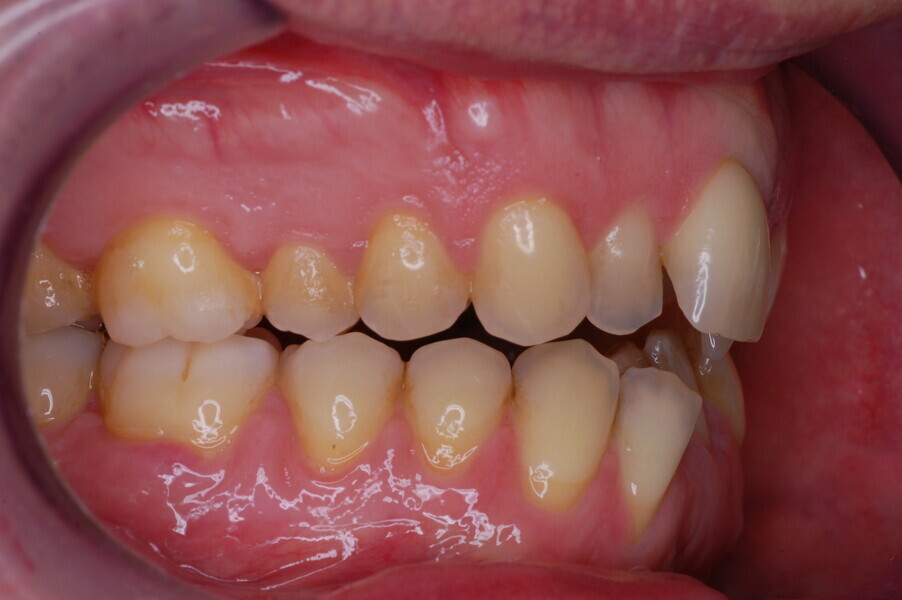

Figs. 1–8: Pretreatment facial and intra-oral photographs.

From the periodontal point of view, the patient showed a good attitude to oral hygiene, but crowding of the mandibular incisors made cleaning difficult in that area, causing plaque accumulation and localised gingival inflammation. The panoramic radiograph revealed the presence of the mandibular third molars and confirmed the absence of the mandibular right central incisor (Fig. 10).

The cephalometric analysis showed a skeletal Class II malocclusion (convexity of Point A: 4.9 mm), a slightly retruded chin position (facial depth: 78.1°) and a skeletal open bite tendency (lower facial height: 53.19°; facial axis: 80.58°; Fig. 9). The mandibular incisors were lingually tipped (Li–APog: 9.3°) and retruded (Li–APog: 1.55 mm), and there was an increased inter-incisal angle of 142.9°.